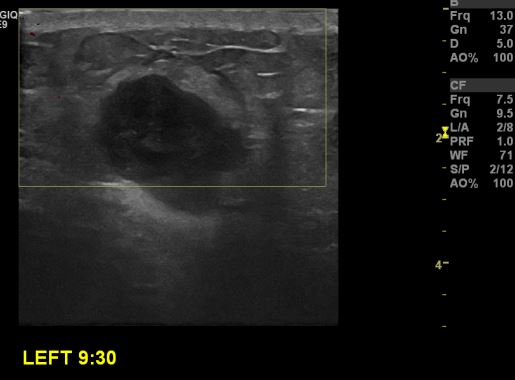

상기환자 좌측 유방에 만져지는 멍울로 내원하신 30대 여성분으로 좌측 9시30분 방향에

만져지는 멍울 조직검사 시행하여 좌측 침윤성 유관암 진단 되었습니다.